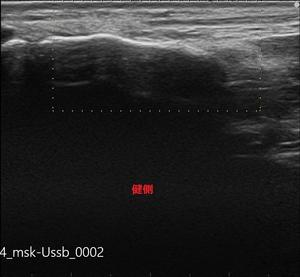

今回はエコー検査を行い、まだ疲労骨折にはいたっていないですが、

このまま無理に動いていると、必ず疲労骨折を発症する為、安静・治療となりました。

中足骨骨膜炎-健側.jpg